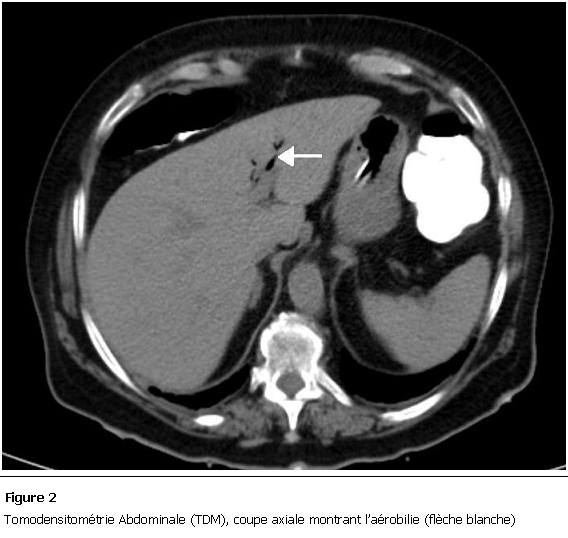

La malade a été mise en condition et une réhydratation a été débutée avec mise en place d’une sonde naso-gastrique avec compensation de la stase gastrique et surveillance de l’état HD et de la diurèse. Devant ce tableau de subocclusion inexpliquée, un scanner abdomino-pelvien a été réalisé et a objectivé des anses grêliques distendues, une aérobilie (Figure 2), et la présence d’un corps étranger de 5cm localisé dans le sigmoïde (Figure 3), le diagnostic d’iléus biliaire a donc été retenu. Devant l’absence des signes de gravité, l’amélioration de la fonction rénale quelques heures après le début des mesures de réanimation et devant la localisation distale du calcul, on a décidé de surveiller la patiente et de poursuivre le traitement médical.

Figure 2:

Tomodensitométrie Abdominale (TDM), coupe axiale montrant l’aérobilie (flèche blanche)